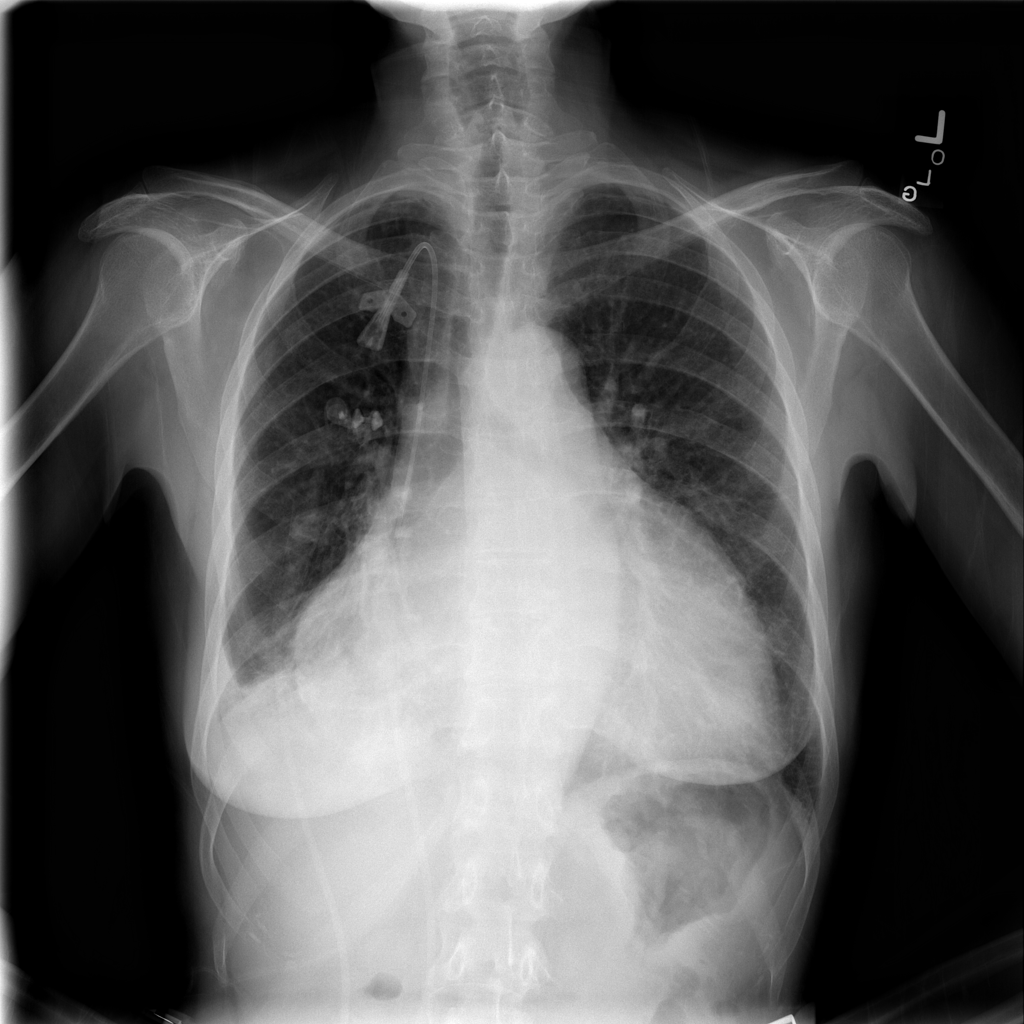

PAT-4639 · IMG-021Effusion

PAT-4639 · IMG-021

PA